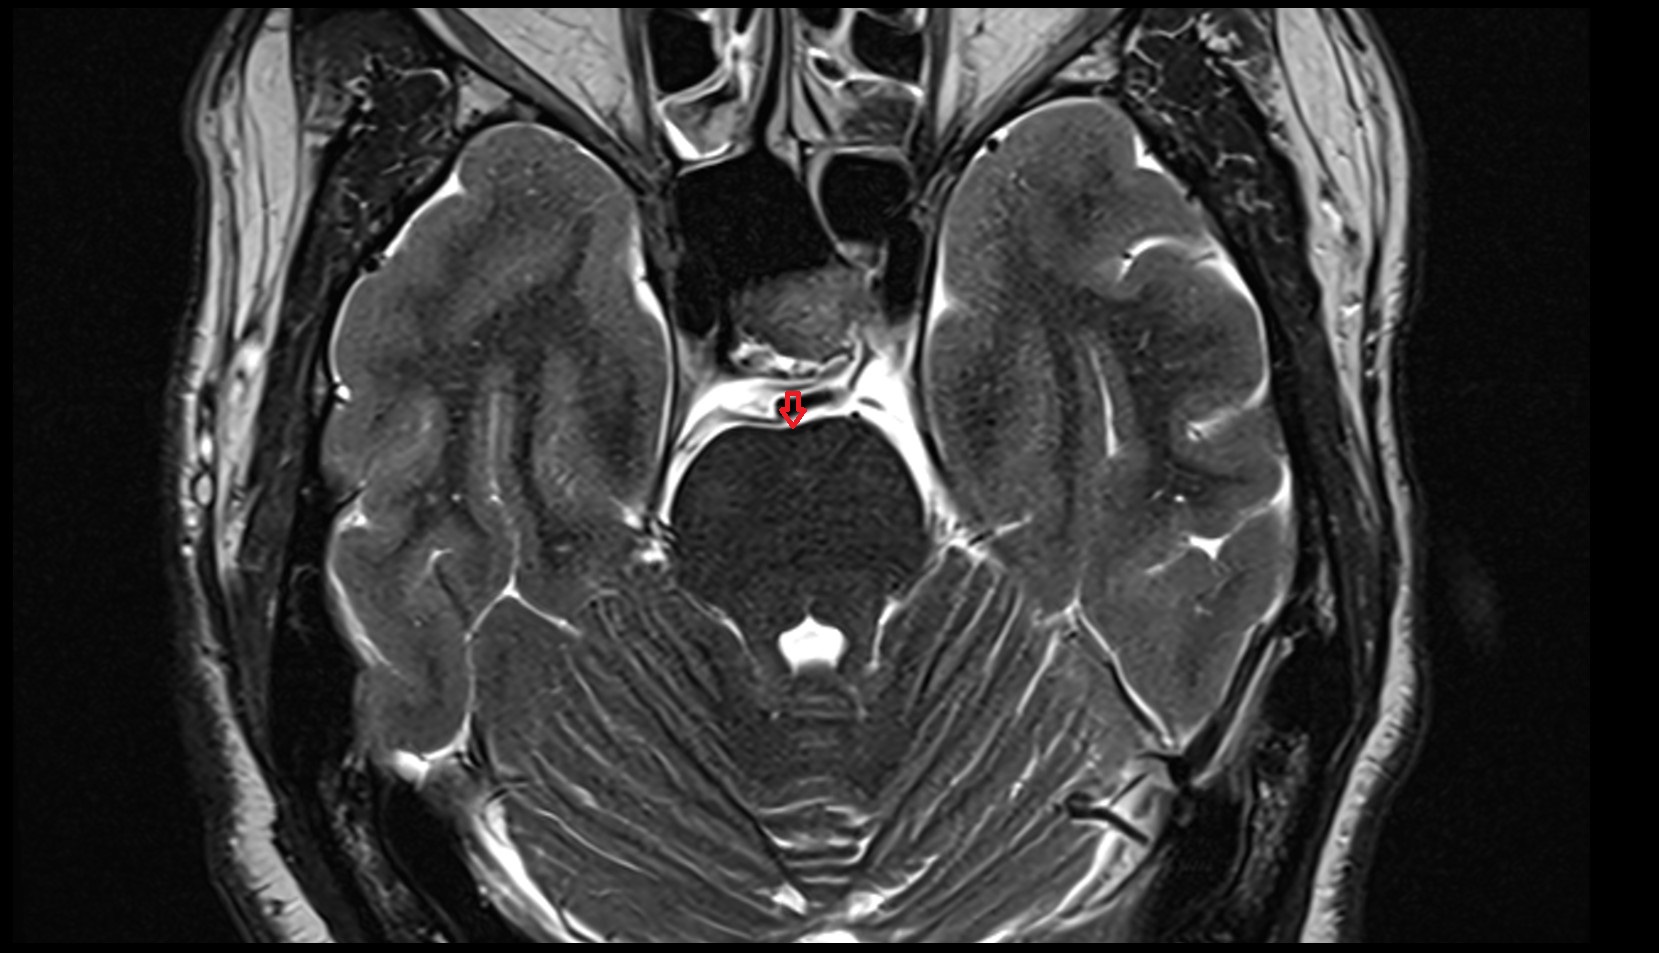

- Median aperture of fourth ventricle (foramen of Magendie)

- Lateral aperture of fourth ventricle (foramen of Luschka)